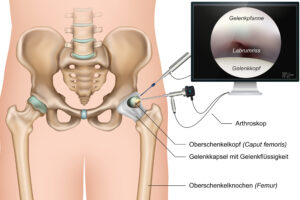

What Is Hip Arthroscopy? Hip arthroscopy is a minimally invasive hip surgery. Doctors use it to look inside your hip joint and treat problems. During this proce

The hip joint is an essential part of your body, connecting your leg to your pelvis. It helps you walk, run, and move freely. However,